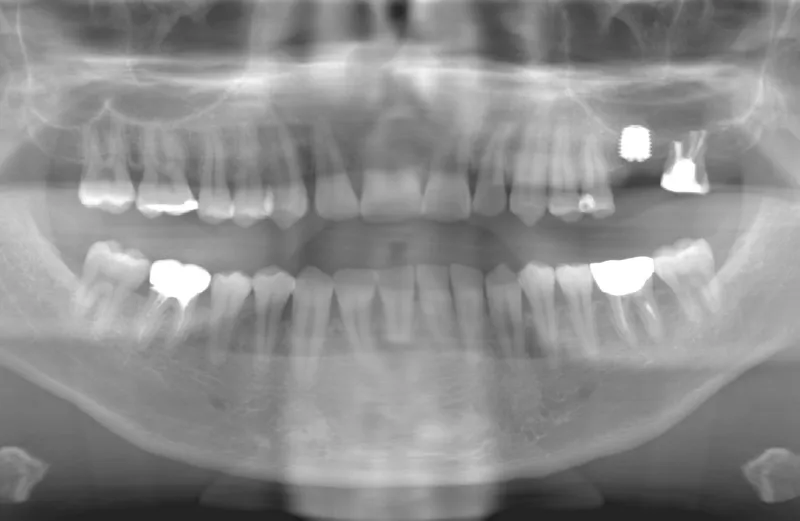

メガジェンオペの症例紹介01

治療前

治療後

| 主訴 | 上入れ歯は以前に入れたことがあるが違和感が強く入れられなかったのでインプラントで治療して欲しい。 他院では上顎洞までの垂直骨量が1~3mm程度しかないのでサイナスリフトが必須であり、インプラント治療で歯が入るまでに1年以上かかると言われたのでセカンドオピニオンを希望で来院。 |

| 治療期間 | 2.5ヶ月で仮歯が入り、 4ヶ月で最終補綴物が入って終了。 |

| 費用 | 約1,500,000円 |

| 治療内容 | エクストラワイドショートインプラントを埋入し、上顎洞を移植材を用いずに挙上しインプラントを埋入した。約2.5ヶ月で仮歯を装着し、様々な機能面に問題がないことを確認し4ヶ月で最終補綴物を装着して終了した。 |

| 治療のリスク | インプラント埋入オペ時に術者が上顎洞内にインプラントを迷入させる可能性がある。これは術者が技術的に熟練していれば防ぐことが可能。 |